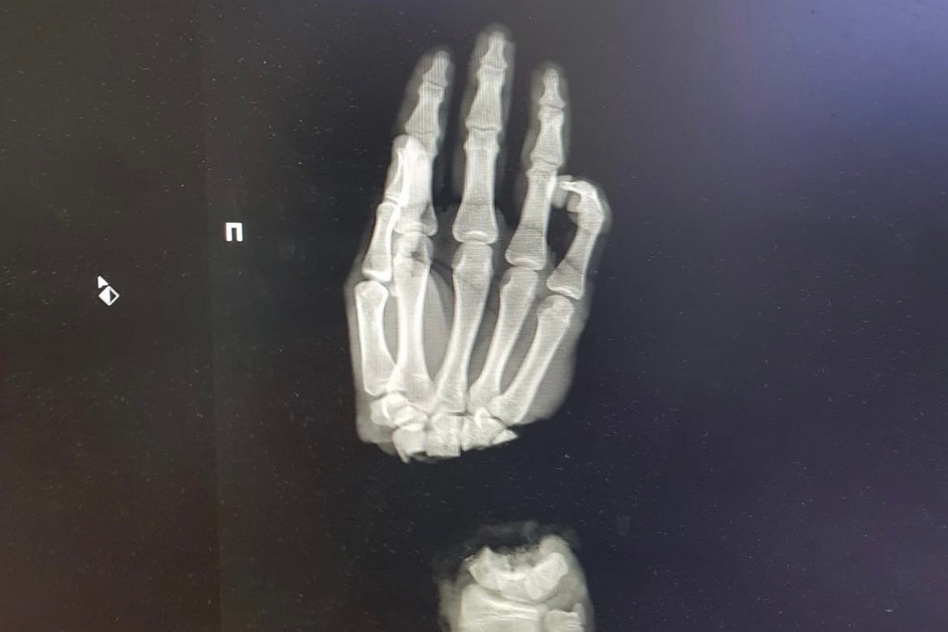

Подростка привезли в Университетскую клинику 1 марта из Коврова, в тот же день вечером врачи провели операцию по реимплантации конечности. Сейчас состояние пациента стабильное, кровоснабжение кисти восстановлено. Понадобится еще несколько операций, чтобы восстановить функциональность кисти насколько это возможно. Отличный результат команды наших врачей!

Медик в качестве иллюстрации приложил рентгеновские снимки до и после операции.